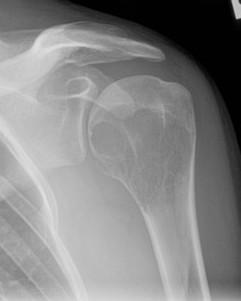

Location

85% meta-epiphysis of long bones

10% axial skeleton (sacrum, vertebral bodies)

X-ray

Eccentric, sharply demarcated lytic lesion

- no sclerosis around lesion

- narrow zone of transition

- metaphysis, extending into epiphysis

- no mineralization